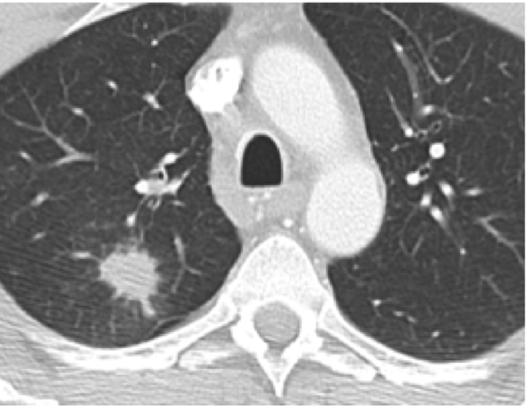

Mynd 6-1 Lítið lungnakrabbamein í hægra lunga (ör) sem fannst við skimun með tölvusneiðmyndum.

Með tilkomu tölvusneiðmyndatækni (TS) varð unnt að finna mun smærri hnúta í lungum en áður var mögulegt með hefðbundnum röntgenmyndum (mynd 6-1). Á síðustu áratugum hefur verið efnt til stórra framvirkra samstarfsverkefna, bæði í Bandaríkjunum og Evrópu. Fyrstu rannsóknir á skimun með TS voru gerðar í Japan og fyrsta alþjóðlega rannsóknin benti til þess að unnt væri að finna um